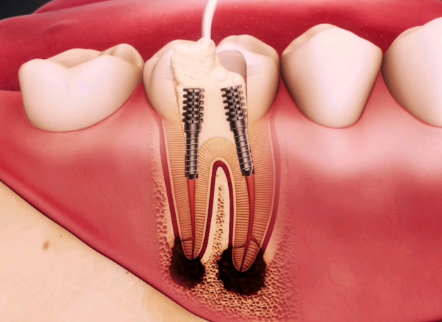

临床常规根管治疗通常需2~3次就诊,相邻两次复诊间隔1~2周,部分感染较轻的患者可通过2次就诊完成全程治疗。就诊次数和间隔并非固定,需结合牙齿感染程度、根管复杂程度调整:急性牙髓炎首次仅做开髓引流缓解疼痛,1~2周后复诊完成后续根管清理、消毒与填充;慢性根尖周炎等重症患者可能需3次及以上复诊,每次间隔仍控制在1~2周,确保炎症充分消退。治疗完成后还需做牙冠保护患牙,患者应遵医嘱复诊并做好口腔护理。